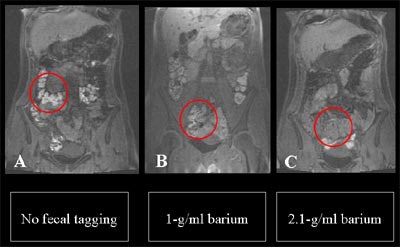

![]() |

| MR colonography without fecal tagging (left) shows higher signal intensity of fecal material compared with image obtained using the 1-g/ml (Micropaque) agent (center). At right, 2.1-g/ml (Maxibar) agent produced the lowest signal intensity. Except for the tagging agent, the protocols (which included four meals without lactulose or iron sulfate) were identical. Images courtesy of Dr. Thomas Lauenstein. |

MR colonography without fecal tagging (left) shows higher signal intensity of fecal material compared with image obtained using the 1-g/ml (Micropaque) agent (center). At right, 2.1-g/ml (Maxibar) agent produced the lowest signal intensity. The protocols, including four meals plus lactulose and iron sulfate, were otherwise identical. Image courtesy of Dr. Thomas Lauenstein.